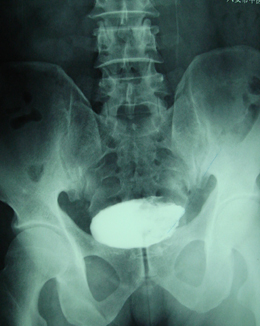

典型病例,男,56岁。无痛性血尿3月。

膀胱占位性病变,呈菜花状生长,考虑膀胱癌。 期待病理。